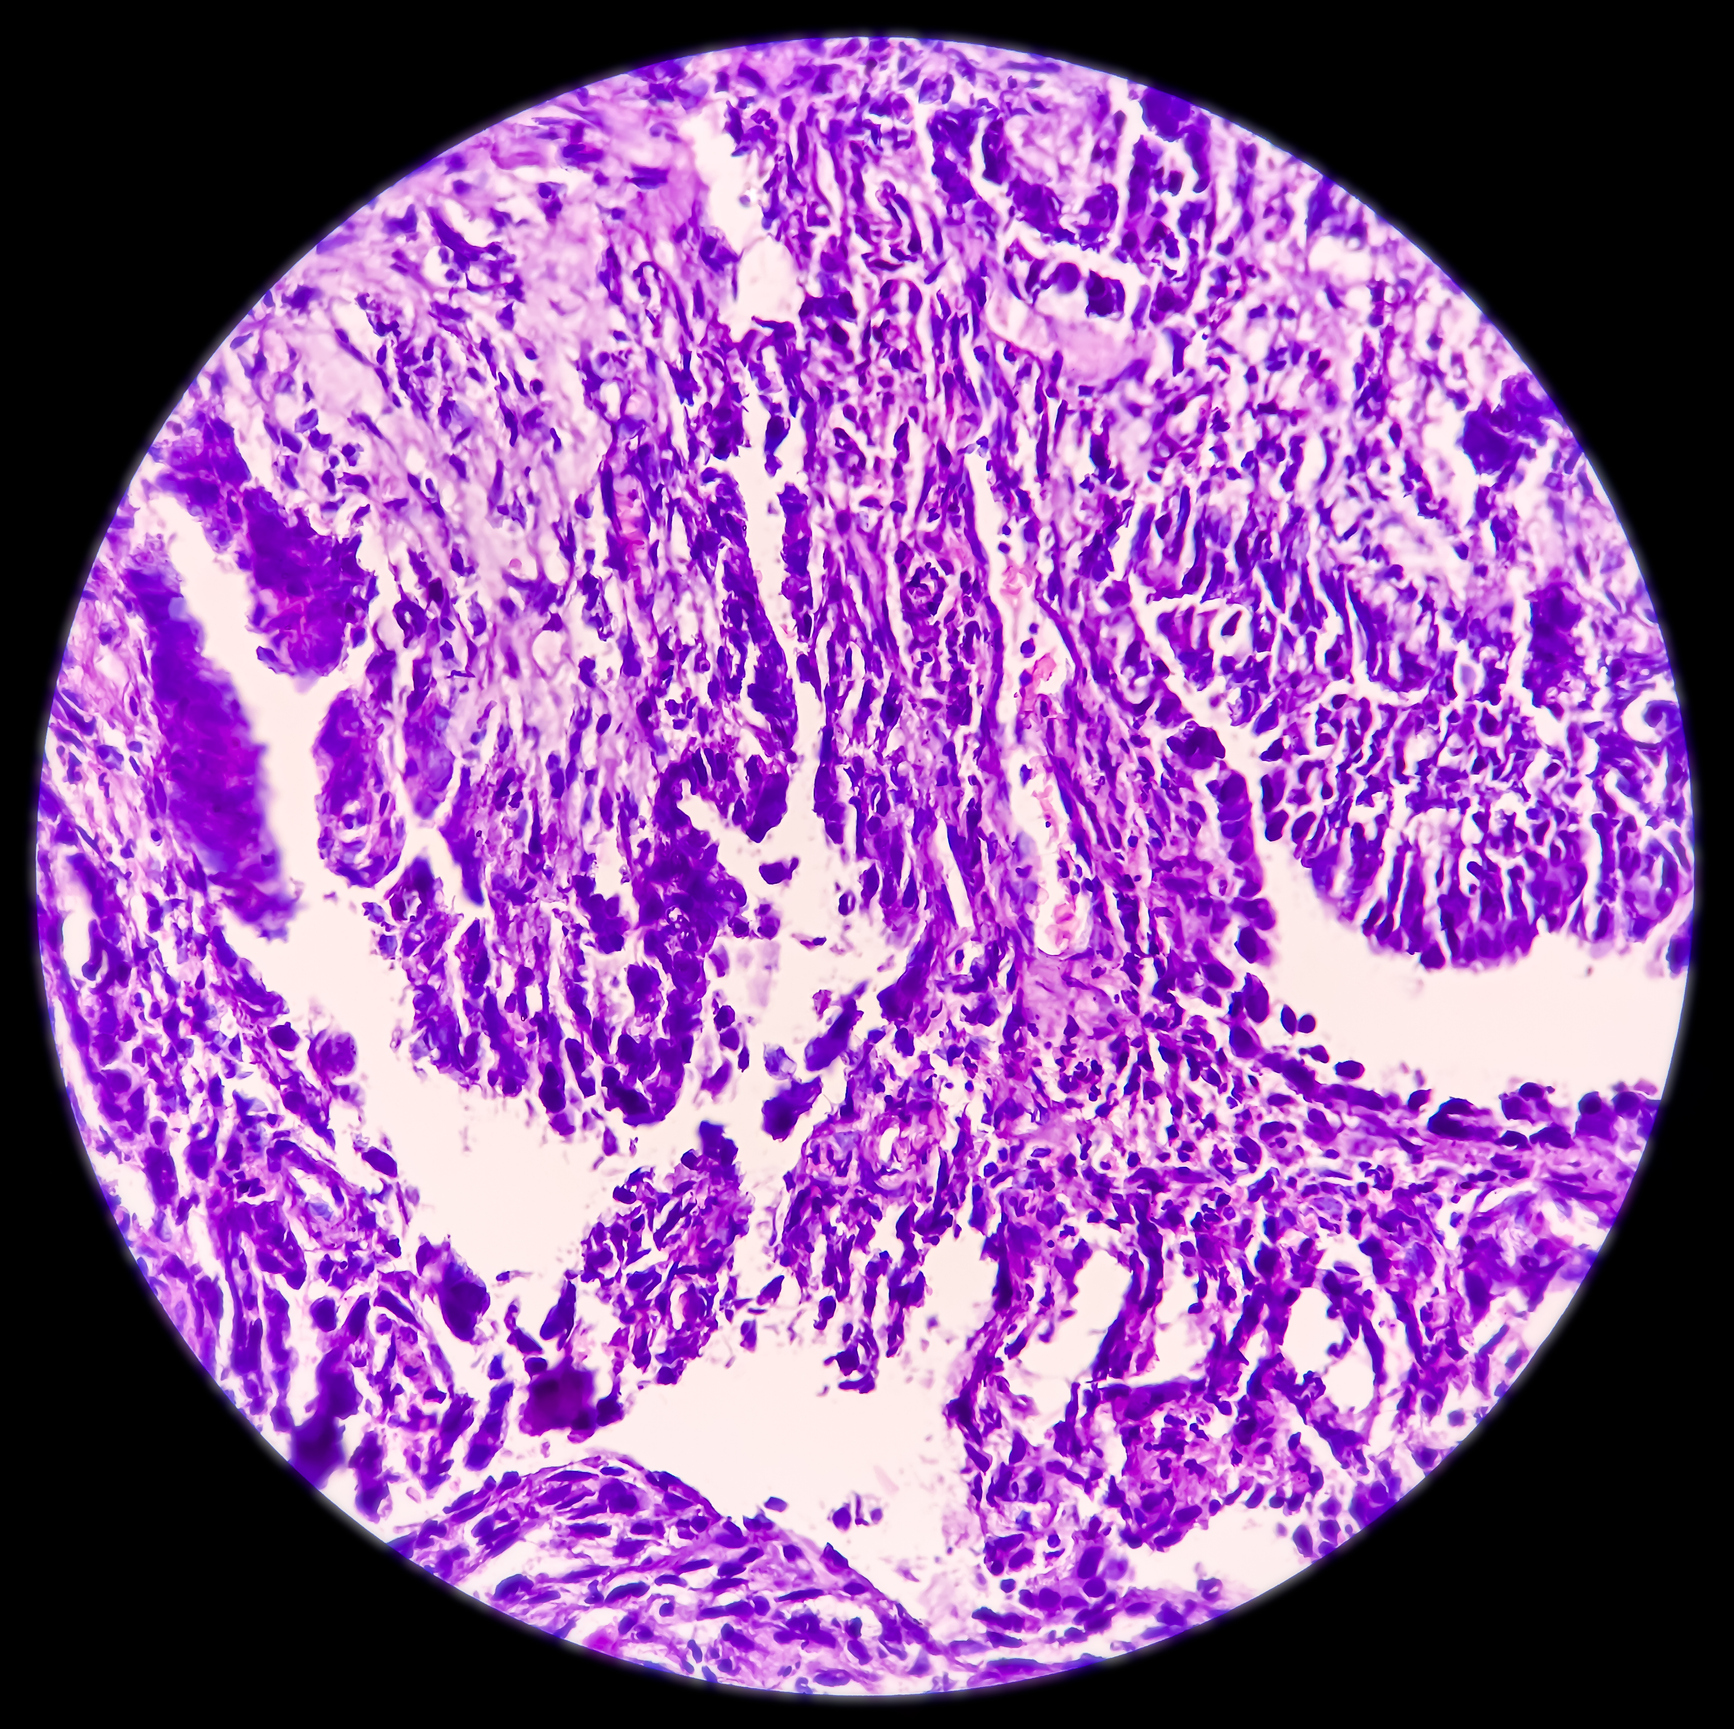

В качестве источника ГИСО рассматриваются интерстициальные клетки Кахаля или соответствующие клетки-предшественники. 60–70% ГИСО представляют собой веретеноклеточные опухоли, 20–30% — эпителиальные или смешанные опухоли. Основным иммунногистохимическим признаком ГИСО является экспрессия KIT [CD117] и DOC-1, подтверждаемая в 95% опухолей.